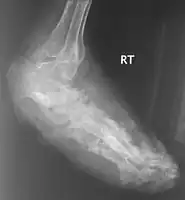

X rays and ultrasonography may be carried out to assess the extent of the disease. X rays findings are extremely variable. The disease is most often observed at an advanced stage that exhibits extensive destruction of all bones of the foot. Rarely, a single lesion may be seen in the tibia where the picture is identical with chronic osteomyelitis. Cytology of fine needle aspirate or pus from the lesion, and tissue biopsy may be undertaken sometimes.[9] Some publications have claimed a "dot in a circle sign" as a characteristic MRI feature for this condition (this feature has also been described on ultrasound).[12]